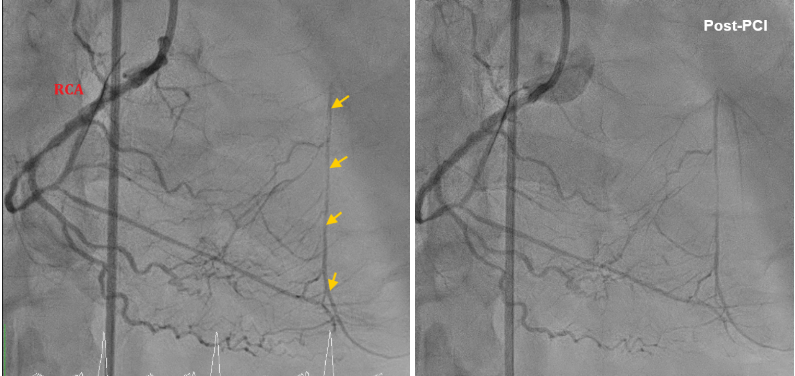

Before the procedure , we had contacted CVS team backed up for a possible emergent ECMO implantation. First, we performed PTCA for RCA successfully and prominent retrograde perfusion at middle-distal LAD via collateral branches from RCA is noted .

After finishing PTCA of LCx, we then coped with LAD CTO. We passed the 1st CTO lesion of LAD with XT-A , successfully advanced to the diagonal branch. However, 2nd CTO lesion was noted over bifurcation of 2nd diagonal branch and LAD. We then advanced SASUKE double lumen catheter with UB3 for better controllability. UB3 was advanced to distal LAD successfully. For the poor economic situation, 2 bare-metal stents were placed at proximal-middle LAD finally. The final angiogram showed an acceptable result. As a result, he had a stable hemodynamic condition peri- and post-PCI. The PCI was successful, efficient(total flouro time 77 min), and smooth. He was discharged with improved symptoms .